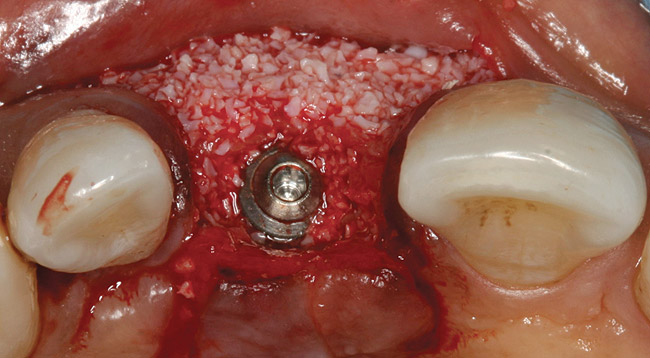

Tapered osteotomes were used to expand the ridge completely to the working length, which was at least 10 mm (Figure 5). It should be noted that if too much resistance is encountered, a drill smaller in diameter than a previously used osteotome can be used along the palatal wall. An implant was then placed into the osteotomy created by tapered osteotomes (Figure 6). Minor cracks were found in the middle of the expanded buccal plate during and after implant placement. Particulate bone allograft (freeze-dried bone allograft) was used to fill the gap between buccal and palatal alveolar plates, and another bone graft (bovine bone mineral) was packed outside the expanded buccal plate. A resorbable membrane was placed over the buccal plate and bone grafts (Figure 7 and Figure 8).

Figure 7  Bone grafts placed for buccal augmentation.

Figure 7